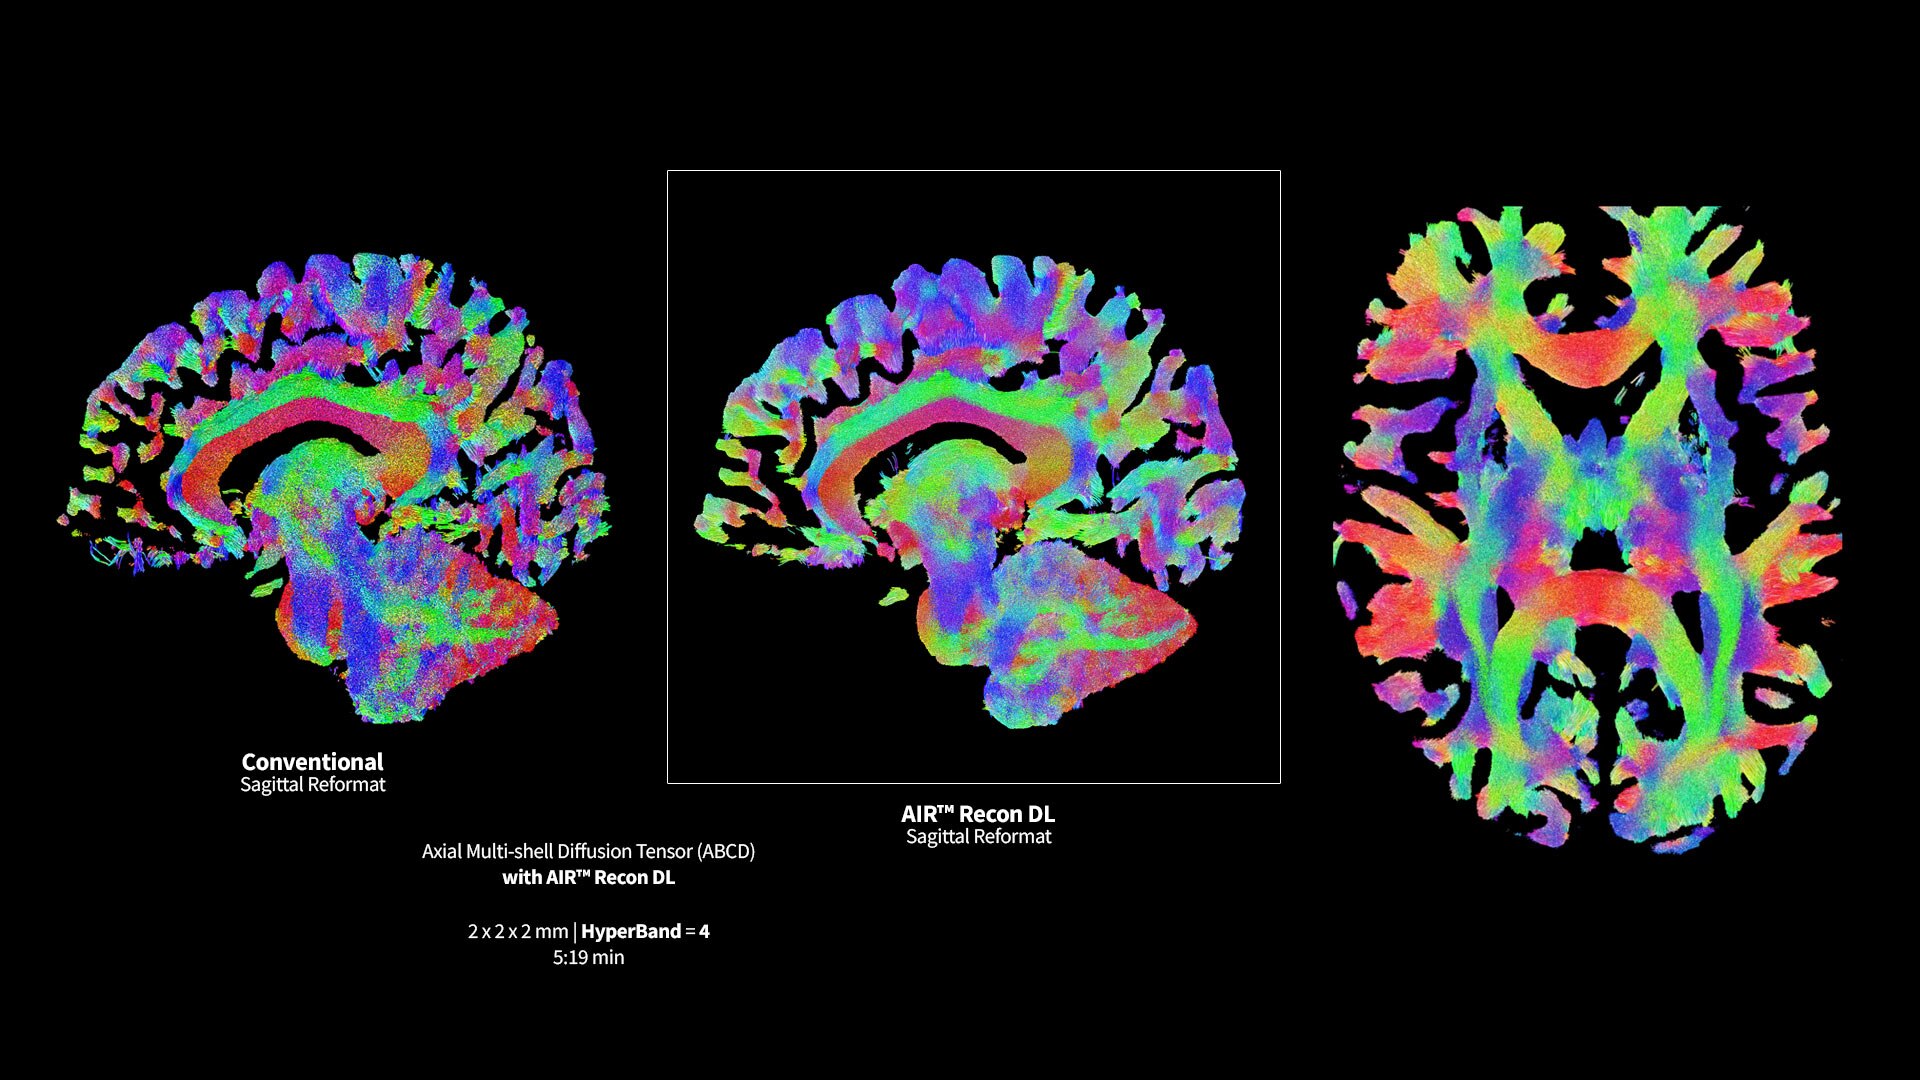

AIR™ Recon DL has revolutionized MR imaging with deep-learning based image reconstruction increased image quality, reduced scan time and improved SNR.